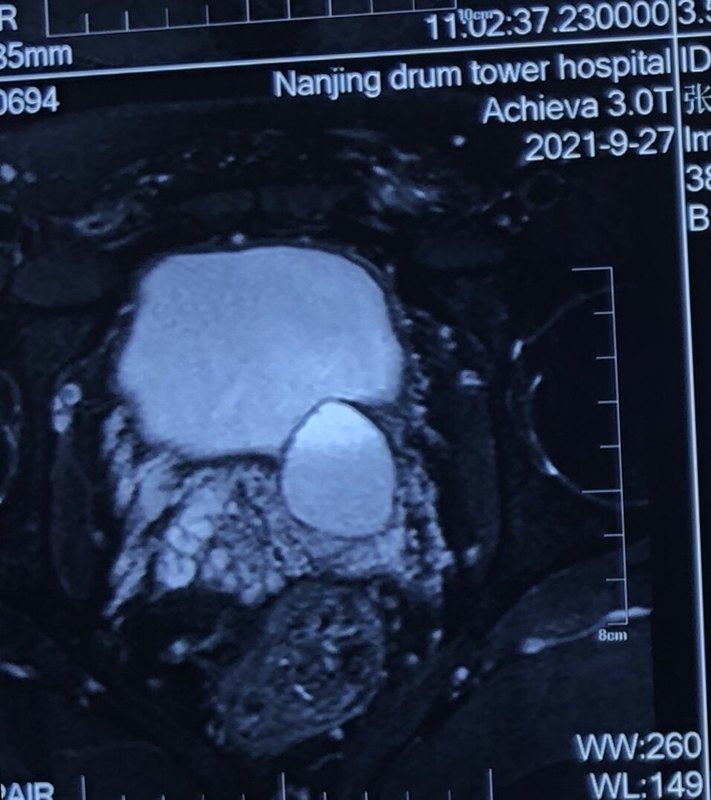

頑固性血精多年,在某外地省醫(yī)科大學(xué)第一附屬醫(yī)院曾經(jīng)做過(guò)一次精囊鏡手術(shù),當(dāng)時(shí)手術(shù)后有大出血。手術(shù)后血精癥狀一直沒(méi)有改善緩解。 保守治療一段時(shí)間后決定再做一次精囊鏡手術(shù)。 昨天手術(shù)日,手術(shù)中發(fā)現(xiàn)左側(cè)精囊囊腫較大,頂向膀胱,囊腫內(nèi)充滿陳舊性團(tuán)塊狀絮狀淤血,前列腺小囊內(nèi)多枚小結(jié)石。予以徹底清理干凈。 術(shù)后第一天恢復(fù)良好。希望能有一個(gè)滿意的手術(shù)效果。 2021.9.29補(bǔ)記